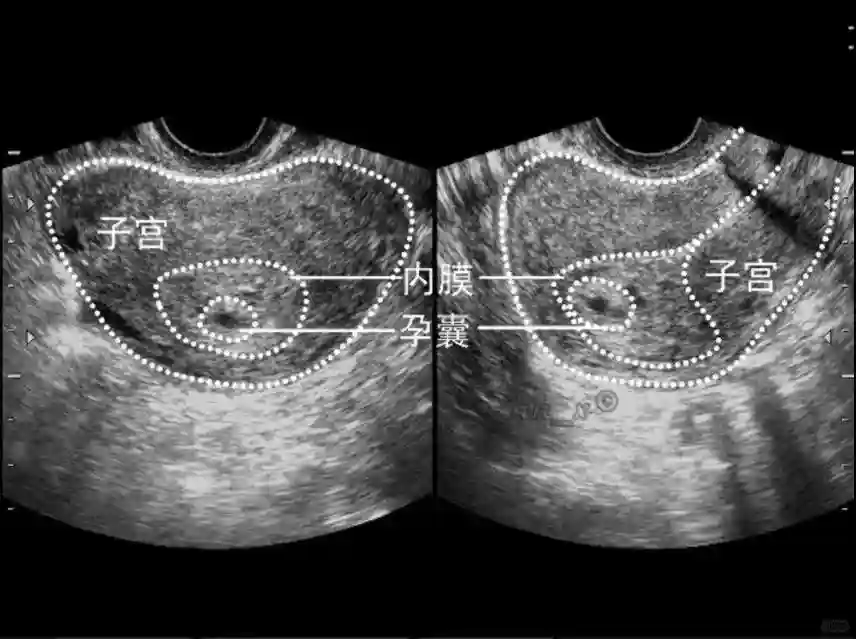

1️⃣妊娠囊:早期妊娠囊:正常妊娠囊位于宫腔上段,表现为宫腔内圆形或椭圆形的无回声区,周边为完整的、厚度均匀的强回声环,强回声环厚度≥2mm,强回声是妊娠绒毛的回声,随着妊娠囊的增大,形成特征性的“双环征” ,10周以后消失。正常的妊娠囊增长速度是平均 1 mm /d。